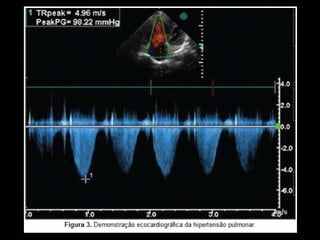

Ecocardiografia

Método não invasivo mais preciso para avaliar a

presença de HAP;

Possibilidade de medições durante esforço cardíaco,

resposta a um exercício ou agente inotrópico;